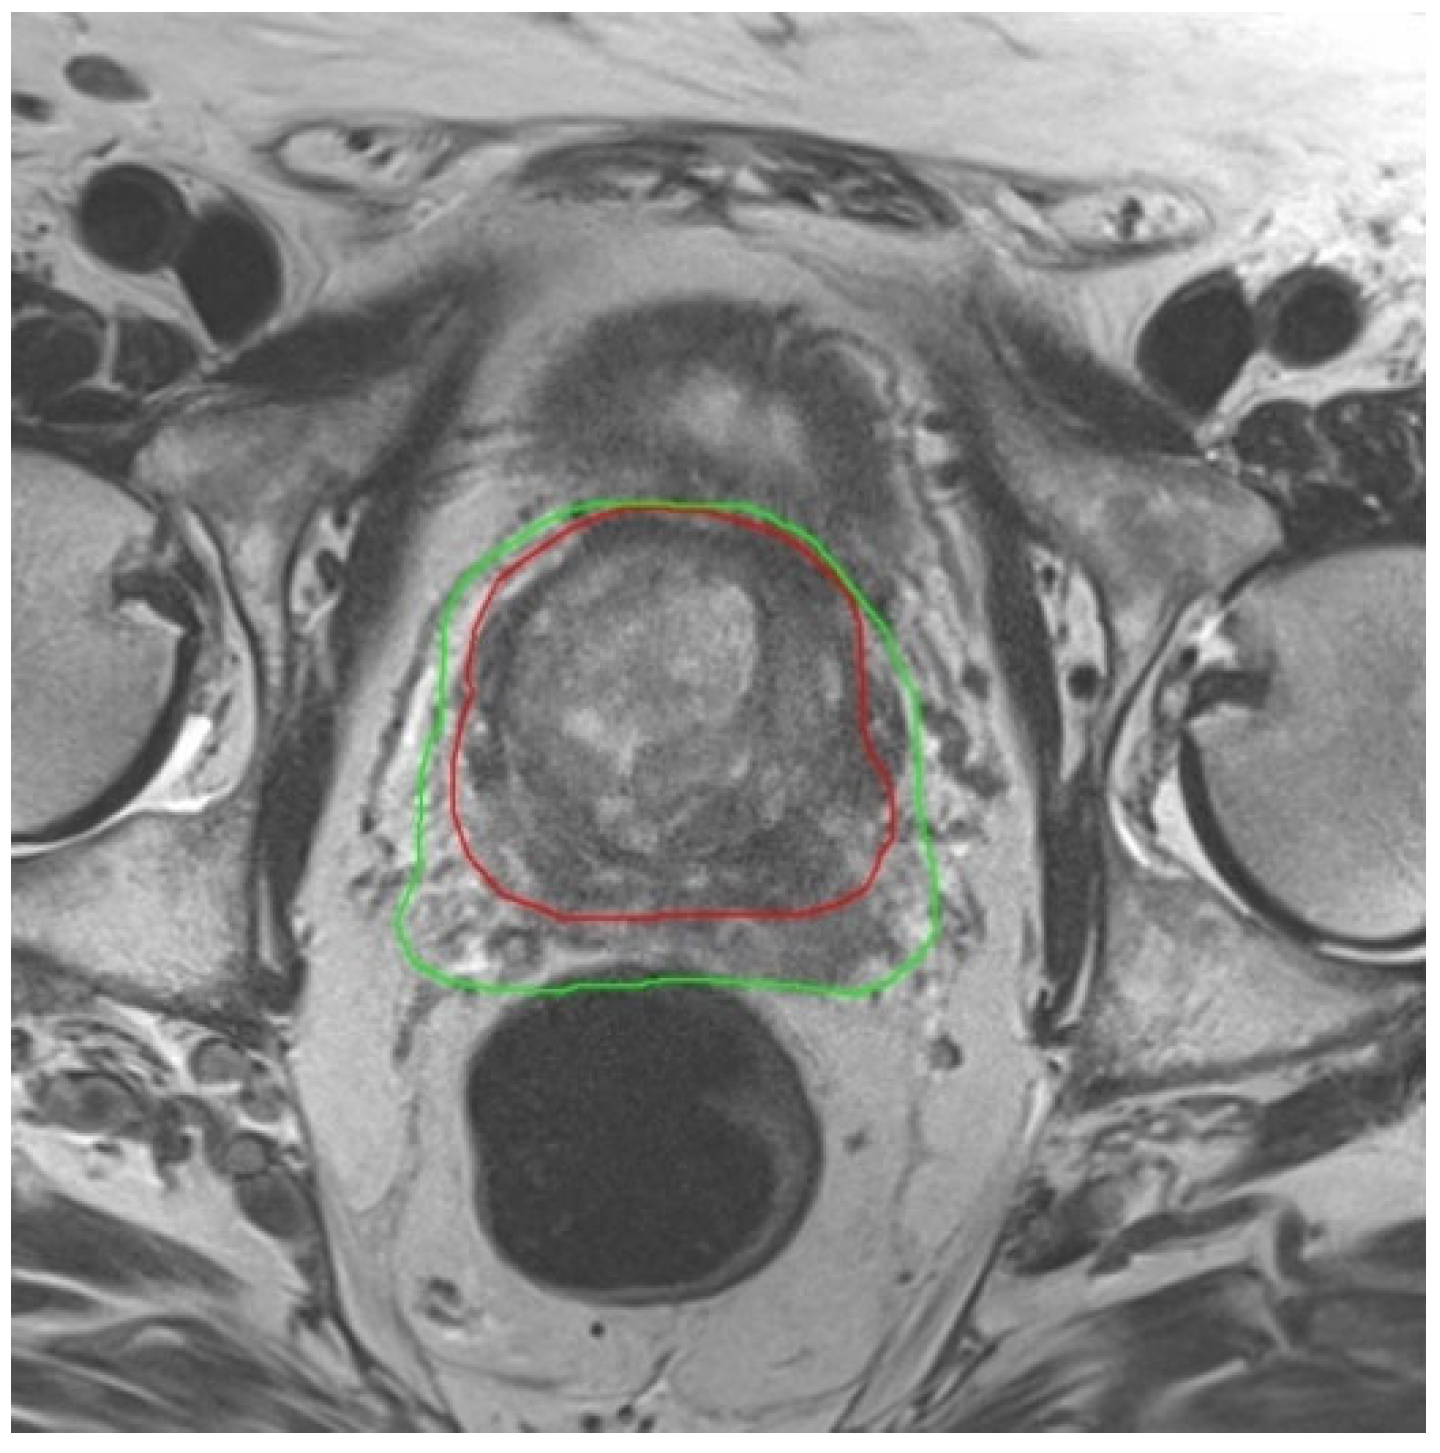

| Prostate Volume Before ADT [cm3] | 88.3 ± 42.9 * | 47.6 | 226.4 |

| Prostate Volume After ADT [cm3] | 66.4 ± 34.3 * | 37.5 | 182.2 |

| Reduction in Prostate Volume During ADT [cm3] | 22.0 ± 15.9 | 3.4 | 57.3 |

| Reduction in Prostate Volume During ADT [%] | 23.7 ± 13.5 | 4.7 | 47.2 |